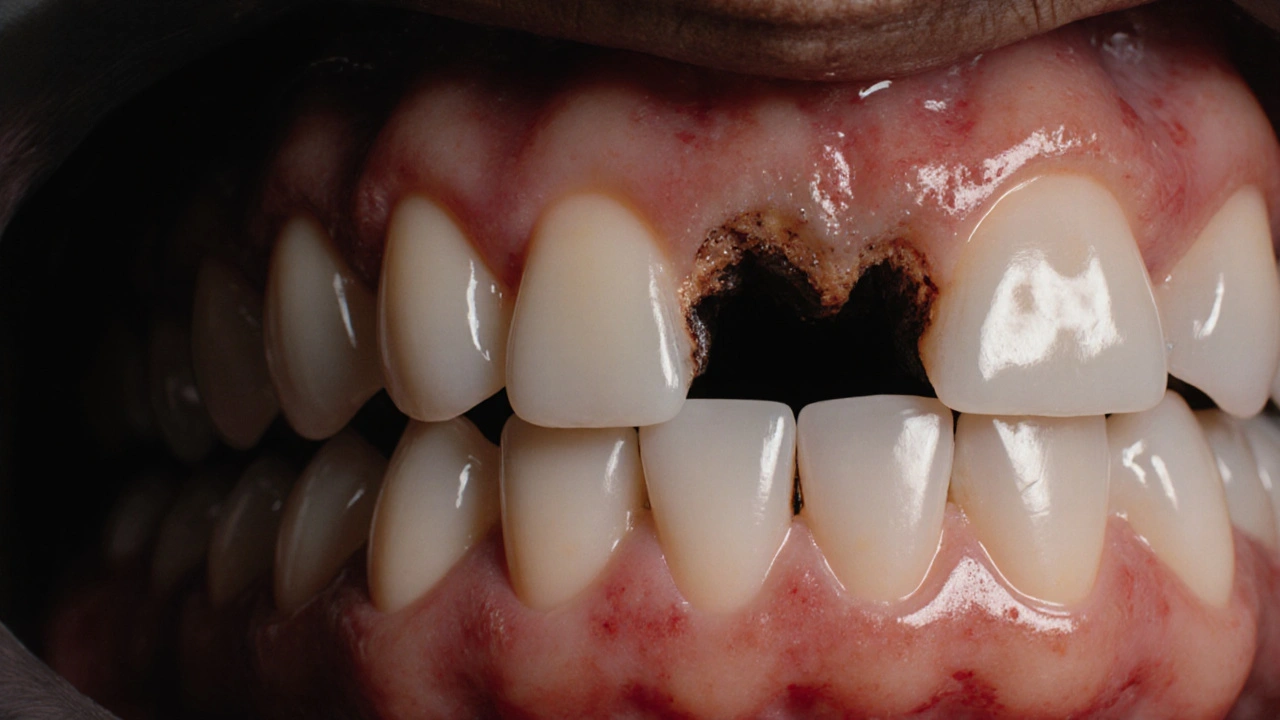

První příznaky, jako jsou citlivost na studené nebo horké, diskomfort při kousání nebo červené dásně, nesmí být ignorovány. Například prasklý kořen může být snadno přehlédnut, ale pokud se objeví bolest nebo otok, je dobré se podívat na článek „Jak poznat prasklý zubní kořen a zachránit svůj úsměv“, kde najdete konkrétní symptomy a kroky, jak získat pomoc rychle.